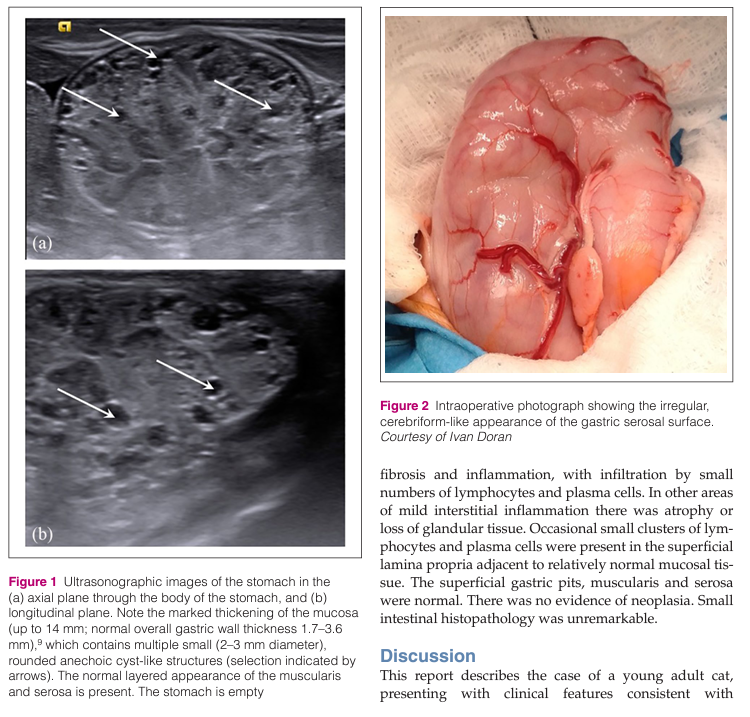

거대 비대성 위염을 보이는 메네트리예 병의 고양이에서의 첫 번째 진단 보고 케이스이다. Ménétrier-like disease

개에서는 종종 보고되지만 고양이에서는 보고된 바가 없어 고양이 수의사들에게도 낯선 질환으로 보아야 한다.